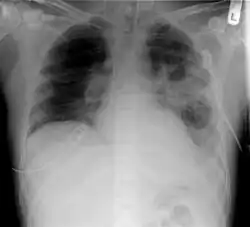

El diagnóstico se basa en criterios clínicos (síntomas, antecedentes patológico) y radiológicos (infiltrado en la radiografía de tórax)[2] Los individuos con signos o síntomas de neumonía deben ser evaluados por un profesional de la salud especializado. El examen físico mostrará cambios patológicos, tales como hiperventilación, hipotensión arterial, taquicardia y cambios en el porcentaje o presión de oxígeno en la sangre. Por medio de la palpación y la percusión se pueden identificar regiones en el pulmón que carecen de la resonancia clásica del tórax, como sería el caso de áreas con fluidos denominados consolidación.

La radiografía del tórax,[26] exámenes de sangre y de esputo en busca de microorganismos infecciosos y otras pruebas de sangre se usan con mucha frecuencia para el diagnóstico de individuos en quienes se sospecha una neumonía. Todos los pacientes con neumonía adquirida en la comunidad deberían tener el oxígeno sanguíneo monitorizado por alguna forma no invasiva de oximetría. Ello ayuda a determinar la función pulmonar en relación con la perfusión sanguínea. En algunos casos se requerirá tomar gases arteriales con ese fin. El conteo de una hematología completa revela la cantidad de glóbulos rojos y si el paciente tiene o no anemia. Es posible que muchos de estos valores, incluyendo la radiografía, salgan normales. Por ello ciertos grupos y organizaciones de salud, como la Sociedad Británica de Tórax no recomienda el uso rutinario de radiografía de tórax en el manejo ambulatorio de pacientes con neumonía.[5] Igualmente, existe un número de enfermedades que se parecen mucho a los resultados de una neumonía, tales como una insuficiencia cardíaca congestiva u otros tipos de daños pulmonares.[27] La radiografía y otros estudios de imagenología permiten confirmar el diagnóstico clínico de una neumonía y diferenciarla de otras patologías respiratorias y cardíacas.[5]